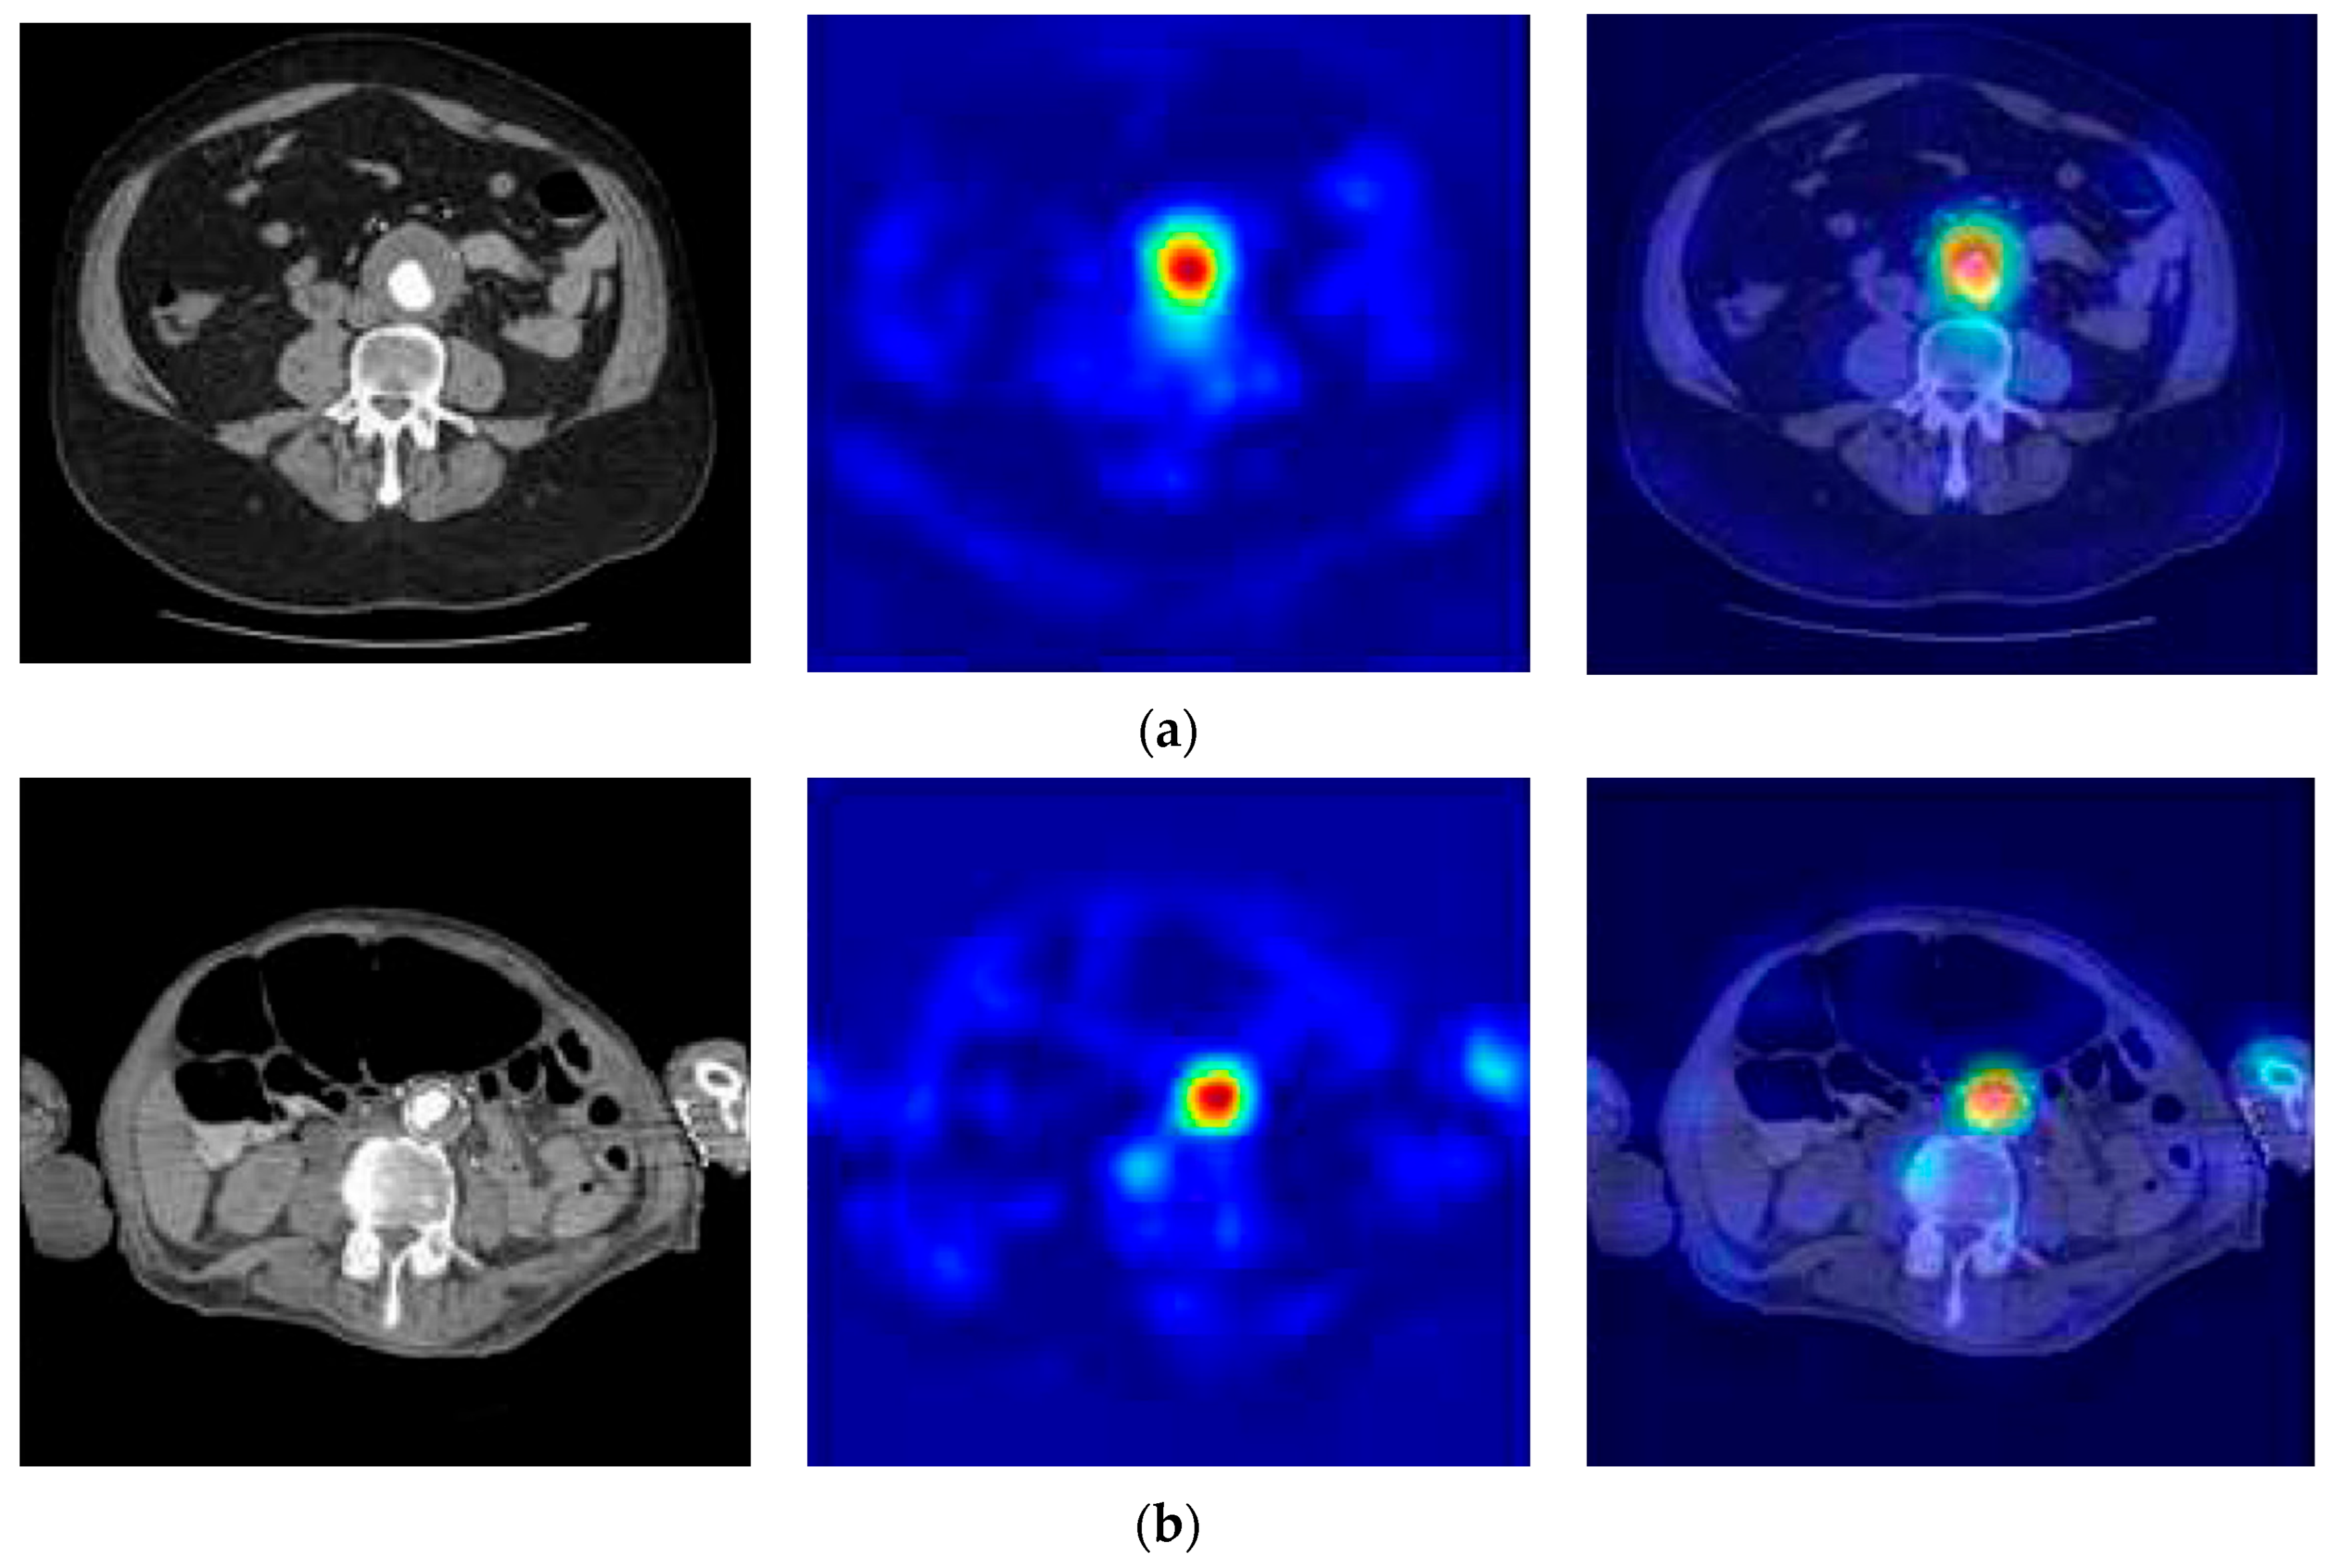

2.2. Abdominal Aortic Aneurysm (AAA) Detection

2.3. Abdominal Aortic Dissection (AAD) Detection